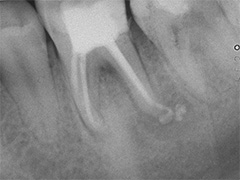

Als Zufallsbefund entdeckter, bis dahin beschwerdefreier apikaler Prozess an Zahn 36. Dessen insgesamt stark verengtes Innenraumsystem gestattete damals in erster Sitzung nur die Darstellung von 2 Kanälen. Wenn intensivstes Weitersuchen erfolglos bleibt, ist dem erfahrenen Behandler irgendwann zumindest so viel über den fehlenden Kanal bekannt: Er kann nicht sehr grosslumig sein und die Weitersuche auf den nächsten Termin zu verschieben ist nicht sehr riskant. Oft genug erlebt, gelingt dann frisch mindreseted und brainrebooted das in Sekunden, was zuvor in 20 min nicht gelingen mochte. So auch hier geschehen, bei der Suche nach dem 3. Kanal.

2 Aufnahmen sind von 2002 und die dritte vom 01.11.2010